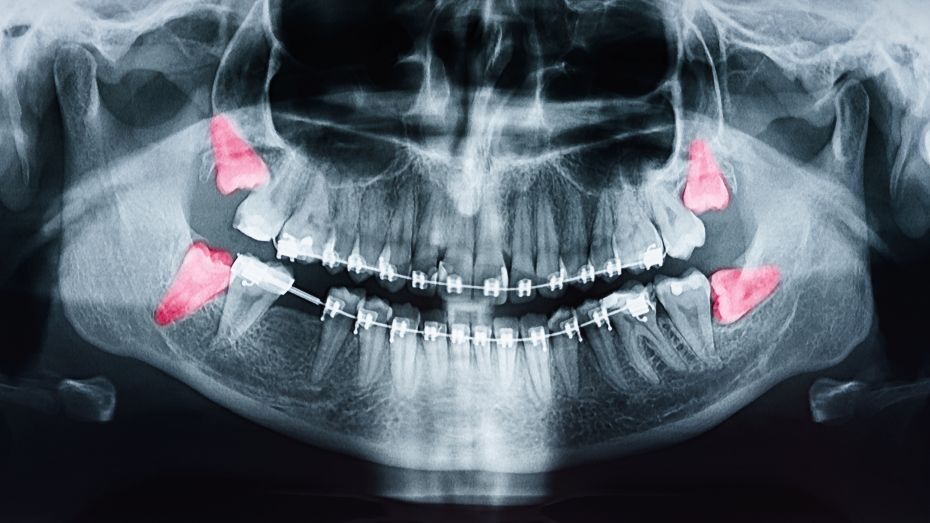

Since you don’t get your wisdom teeth until your permanent teeth are already in place, your extra molars could push them out of alignment. This can create a variety of oral health issues, including bite problems, overcrowding, and even pain. Worse yet, if they’re growing sideways, they can even break the roots of nearby teeth, requiring additional treatment to correct.

Your jaw is essential to your ability to eat, drink, speak, smile, and laugh. When your wisdom teeth become impacted within the jaw, they can shift your other teeth out of alignment, and it can even cause cysts to form alongside them. These in turn can hollow out your jawbones and damage the nerves of the surrounding teeth!

Maintaining excellent oral hygiene is the number one way to ensure that your smile lasts a lifetime. This includes brushing your teeth twice a day and flossing daily. Unfortunately, because wisdom teeth erupt at the very ends of your arches, they can be difficult to reach when cleaning your mouth. Thus, they become more susceptible to dangerous plaque buildup, cavities, and gum disease.